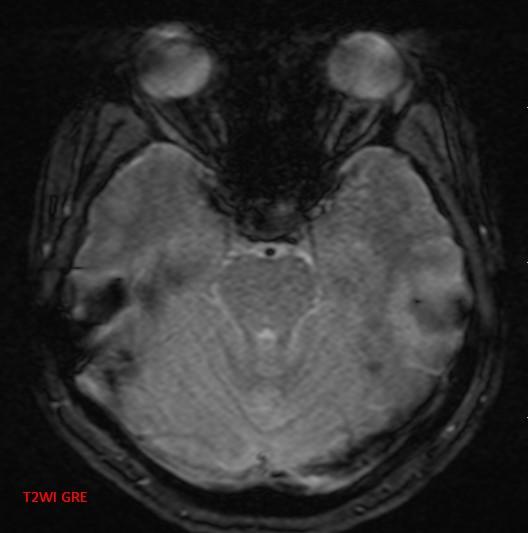

*30-year-old pregnant woman with headache and diplopia.

What is the most likely diagnosis?

Answer: Pituitary apoplexy

MR images reveal an ovoid lesion (red arrows) in the pituitary fossa with suprasellar extension. The optic chiasm is compressed (yellow arrows). The lesion is T1 and T2 hyperintense showing blood-blood fluid level (blue arrows).

MRI typically demonstrates a pituitary region mass. The imaging characteristics of blood on MRI are variable and change with the age of the blood (2, 3).

• T1: variable signal.

• T2: variable signal.

• T1 C+: enhancement variable; usually peripheral.

• DWI: restricted diffusion can be present in solid infarcted components